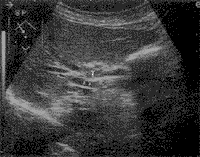

肿瘤部位胆管壁局部增厚,相邻血管内侧面平整(↑),超声判断为PV(±),手术发现肿瘤与门脉粘连明显,不能分离为PV(

)

图1 肝门部胆管癌(T)